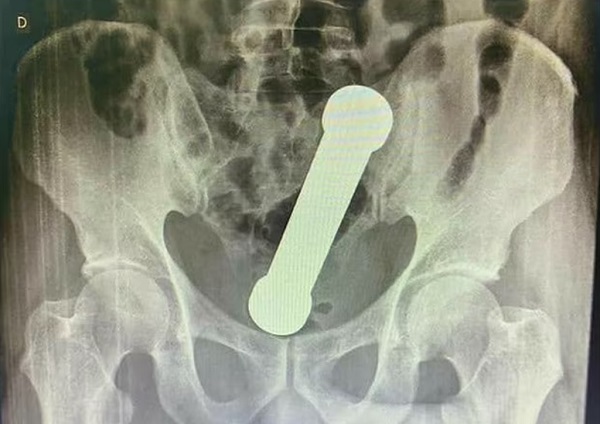

병원 진료를 받게 된 남성은 엑스레이 촬영을 하였으며 엑스레이 사진에는 20cm 길이의 덤벨이 직장과 결장이 만나는 곳에 박혀있는 모습이 포착되었습니다.